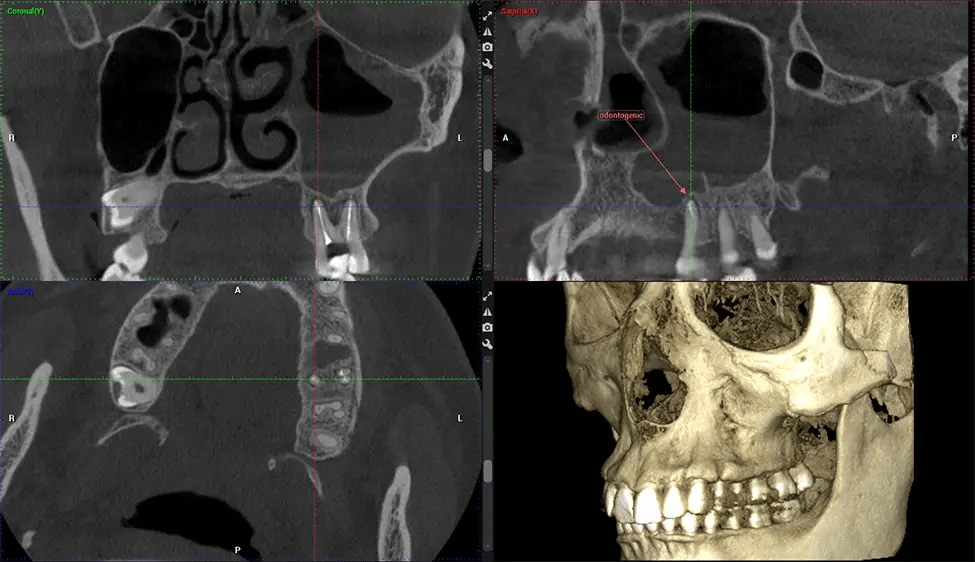

Tomografía computarizada de haz cónico (CBCT) es una técnica de imagen avanzada utilizada en odontología y cirugía maxilofacial para obtener imágenes 3D detalladas de las estructuras orales y maxilofaciales. Dr. G Estudio Dental, nuestro CBCT Los escáneres utilizan un haz de rayos X en forma de cono y un detector especializado para capturar imágenes desde diferentes ángulos. Posteriormente, una computadora combina estas imágenes para crear una representación tridimensional de la anatomía oral del paciente.

Esta exploración 3D, llamada tomografía computarizada de haz cónico, le brinda a su dentista una imagen más completa de su anatomía bucal y sus procesos patológicos que una radiografía tradicional. A diferencia de las radiografías convencionales, que capturan una imagen 2D de la boca desde varios ángulos, una exploración 3D toma varias radiografías digitales para una imagen. Proporciona una vista completa de la mandíbula, los dientes, los nervios y los tejidos blandos. Esta vista mejorada permite a los dentistas detectar problemas menores que no son visibles en las exploraciones 2D tradicionales, como muelas del juicio impactadas o fracturas óseas en la cavidad sinusal.

Hay muchos beneficios al usar CBCT tecnología, especialmente en comparación con el formato tradicional de rayos X 2D. Una de las ventajas más significativas de CBCT La ventaja de las tomografías es que proporcionan mucha más información que las radiografías tradicionales. Una tomografía permite a su dentista ver imágenes de la mandíbula y la boca desde todos los ángulos, incluyendo los senos paranasales, la cavidad nasal, los pómulos y otras áreas circundantes. Esta información adicional ayuda a su dentista a elaborar un plan de tratamiento integral que aborde todos los aspectos de su salud bucal.

Otorrinolaringólogo Diagnóstico de la apnea obstructiva del sueño (AOS) y evaluación de la anatomía de los senos paranasales y la cavidad nasal. Visualiza toda la vía aérea faríngea para medir el volumen, localizar constricciones y planificar una cirugía correctiva si es necesario.